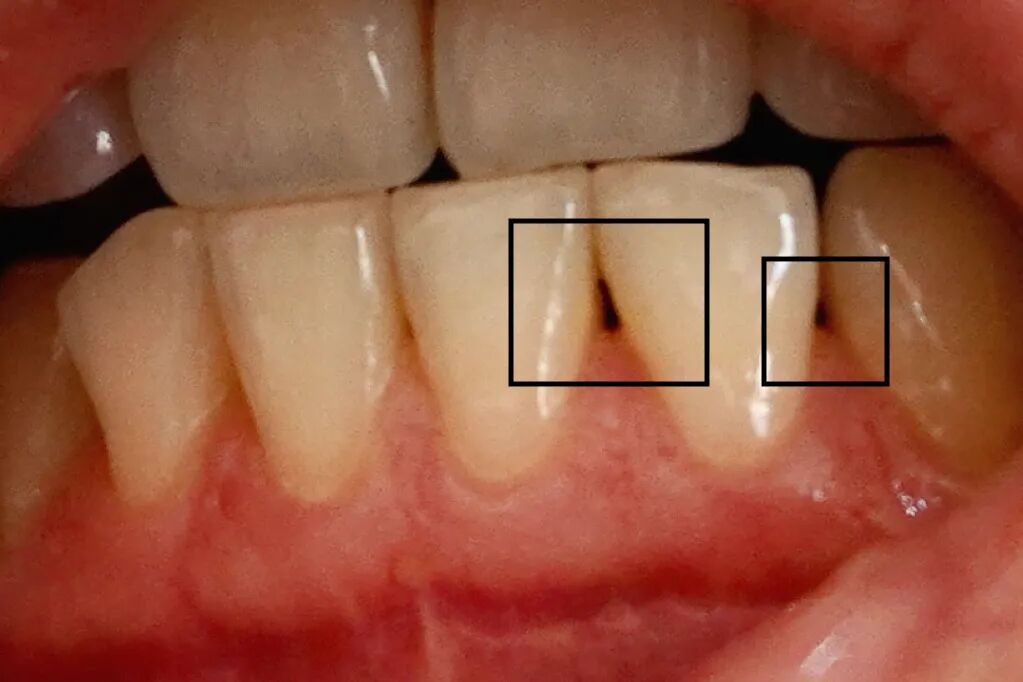

主要表现为牙与牙之间空出了一个「黑三角」、牙根外露得越来越严重、牙龈变薄、牙缝看起来也宽了不少——真·喝凉水都塞牙!

图片来源:小🍠